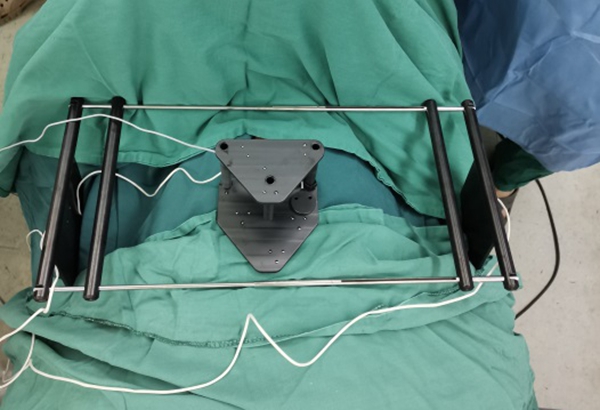

2020年1月9日,骨二科(脊柱外科)王栋教授团队成功将电磁导航技术引入到脊柱手术中,开展了医院首例电磁导航腰椎后方椎间融合术(PLIF)和首例电磁导航经皮穿刺椎体成形术(PVP)。手术当日,通过简单的安装信号发射器、定位仪并进行2D影像认证后,王栋教授团队在导航的辅助下,轻松完成原先脊柱手术中风险巨大的椎体植钉过程,随后的椎管减压及水泥注入等步骤一气呵成,有效缩短了手术时间、术中投射次数,大大降低了手术风险。